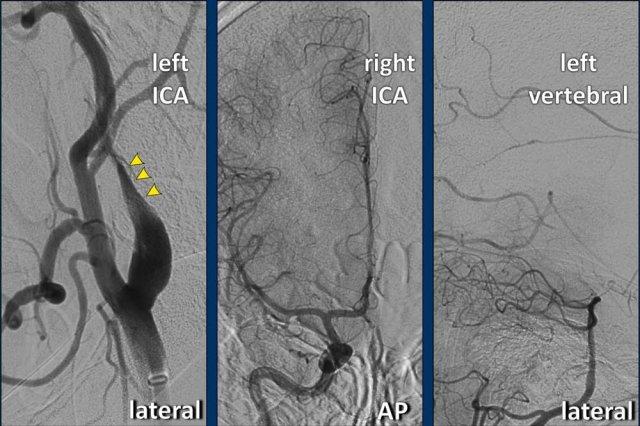

Bóc tách trên DSA

Tất cả các dấu hiệu đã thảo luận trên CTA đều tương tự và thậm chí rõ ràng hơn trên DSA.

- Catheter được đặt tại mức phình cảnh (bulbus), có hình ảnh bình thường.

Vài centimet phía trên phình cảnh, lòng mạch ICA bị lệch tâm và bị chèn ép bởi khối máu tụ thành mạch (thấy rõ hơn trên hình chi tiết số 2).

Tại mức nền sọ (đường chấm vàng), mạch máu trở về bình thường. - Hình chi tiết cho thấy thuốc cản quang đã thâm nhập vào trong khối máu tụ.

Lưu ý tổng đường kính ICA bị giãn rộng. Mũi tên chỉ lòng mạch thật sự. - Sau điều trị nội mạch, sự thông thoáng của ICA đã được phục hồi.

Khối máu tụ thành mạch phần lớn đã được tiêu huyết khối thông qua điều trị tĩnh mạch bằng chất hoạt hóa plasminogen mô tái tổ hợp (rt-PA, alteplase) trước khi can thiệp nội mạch. Vạt nội mạc (intima flap) vẫn còn nhìn thấy. Một lần nữa, bạn có thể thấy vạt nội mạc dừng lại tại mức nền sọ.

Chụp mạch số hóa xóa nền (DSA) ICA trái xác nhận bóc tách (đầu mũi tên) qua hình ảnh cấu hình dạng ngọn lửa ở đoạn gần ICA.

Tiếp theo, DSA của ICA phải và động mạch đốt sống trái được thực hiện.

Chụp mạch ICA phải cho thấy vắng mặt động mạch thông trước (Acom) do thuốc cản quang không đi từ phải sang trái. Ngoài ra, bơm thuốc cản quang vào động mạch đốt sống trái cho thấy vắng mặt động mạch thông sau (Pcom).

Đây là bằng chứng xác nhận chẩn đoán “Động mạch cảnh bị cô lập”.